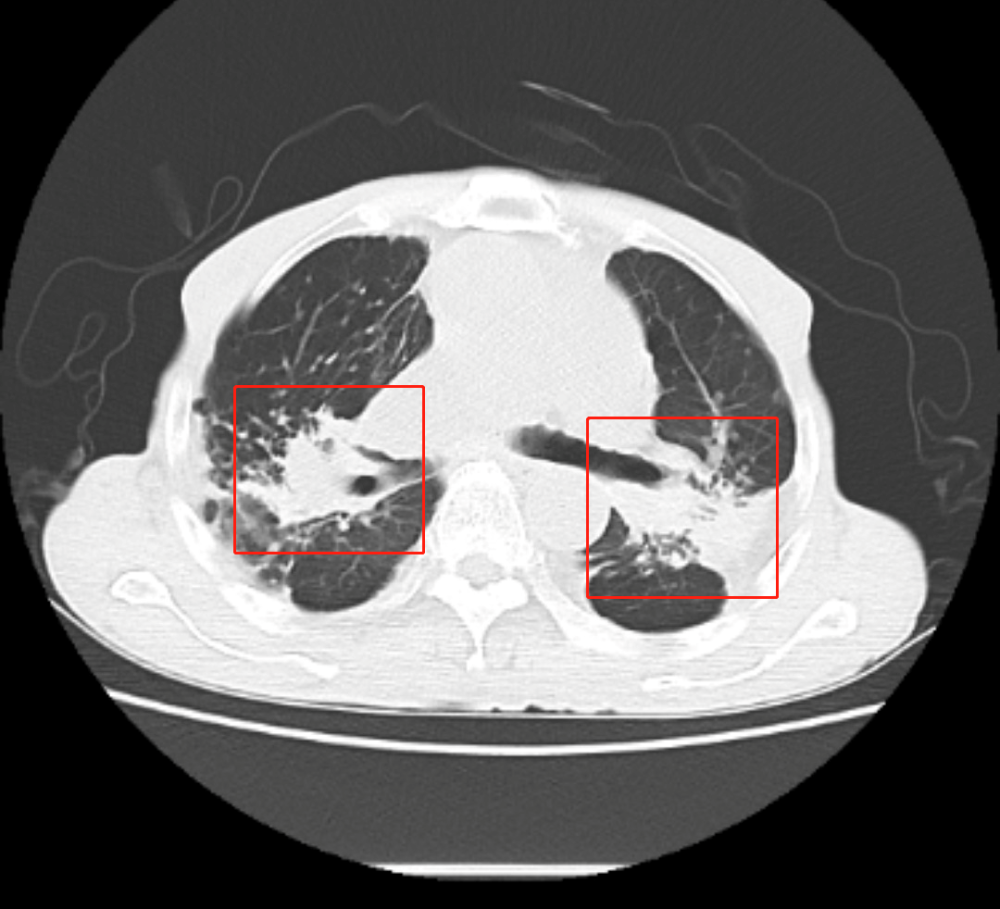

经过入院胸部CT检查 , 可见陈大爷肺内多发由于粉尘沉积引起的肺部肿块 , 融合成团 , 如同白色水泥团块一样 , 紧紧地附着在患者两处肺门的地方 , 初步诊断矽肺 。

陈大爷的CT报告